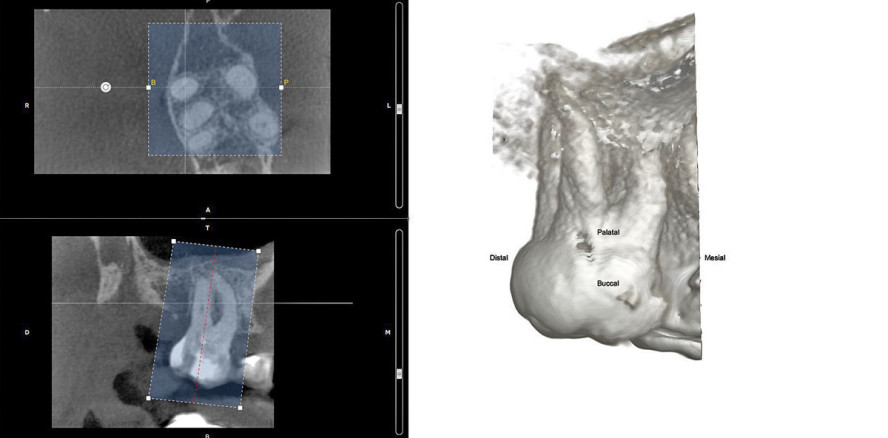

Die Software führt den Benutzer intuitiv durch die einzelnen Planungsschritte. Nach einer Befundung des gesamten Volumens wird dieses auf den relevanten Bereich reduziert (Abb. 2) und die Kanaleingänge und apikalen Foramina jedes Wurzelkanals separat markiert. Die von der Software dreidimensional erkannten Kanalverläufe werden im folgenden Schritt überprüft und können bei Bedarf vom Benutzer korrigiert werden (Abb. 3). Mithilfe der visualisierten Wurzelkanalinstrumente lassen sich koronale Kanalerweiterungen und geradlinige Zugangskavitäten planen (Abb. 4). Die integrierte Feilendatenbank ermöglich eine Auswahl der geeigneten Instrumente, und durch Anpassung der Gummistopper an die jeweiligen Referenzpunkte können die Wurzelkanallängen bereits präendodontisch geschätzt werden (Abb. 5).